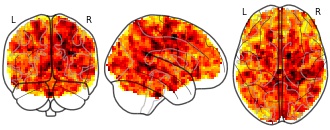

License information was derived automaticallyDescriptionModel EA3: FC ~ average BMI + change BMI + average logmFD + change logmFD + age + sex

Collection description

Obesity imposes serious health risks and involves alterations in resting-state functional connectivity of brain networks involved in eating behavior. Bariatric surgery is an effective treatment, but its effects on functional connectivity are still under debate. In this pre-registered study, we investigated the effects of bariatric surgery on major resting-state brain networks (reward and default mode network) in a longitudinal controlled design.

33 bariatric surgery patients and 15 obese waiting-list control patients (37 females; aged 44.15 ± 11.86 SD years (range 21-68)) underwent magnetic resonance imaging at baseline, after 6 and 12 months. We conducted a pre-registered whole-brain time-by-group interaction analysis, and a time-by-group interaction analysis on within-network connectivity (https://osf.io/f8tpn/, https://osf.io/59bh7/). In exploratory analyses, we investigated the effects of weight loss and head motion.

Bariatric surgery compared to waiting did not significantly affect functional connectivity (FWE-corrected p > .05), neither whole-brain nor within-network. In exploratory analyses, surgery-related BMI decrease (FWE-corrected p = .041) and higher average head motion (FWE-corrected p = .021) resulted in significantly stronger connectivity of the reward network with medial posterior frontal regions.

This pre-registered well-controlled study did not support a strong effect of bariatric surgery, compared to waiting, on major resting-state brain networks after 6 months. Exploratory analyses indicated that head motion might have confounded the effects. Data pooling and more rigorous control of within-scanner head motion during data acquisition are needed to substantiate effects of bariatric surgery on brain organization.Subject species